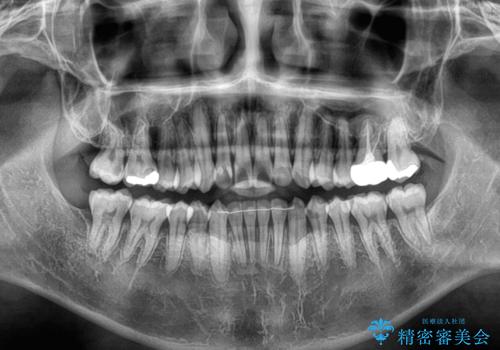

- 前歯のデコボコを気にして来院された患者様です。

前歯が90度近く捻れていたため、しっかりと治すことを考えるとワイヤー矯正の方がおすすめではありましたが、本人の希望によりインビザラインを用いて矯正治療を行うこととしました。

途中2年強の来院がなく、改善されていたデコボコが元に戻ったり、装着時間が不足しており前歯のデコボコは十分に改善することはできませんでしたが、5年間の有効期限内で可能な限り歯列を整えることができました。